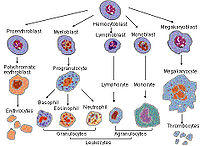

Development

Megakaryocytes are derived from hematopoietic stem cell precursor cells in the bone marrow. They are produced primarily by the liver, kidney, spleen, and bone marrow. These multipotent stem cells live in the marrow sinusoids and are capable of producing all types of blood cells depending on the signals they receive. The primary signal for megakaryocyte production is thrombopoietin or TPO. TPO is sufficient but not absolutely necessary[2] for inducing differentiation of progenitor cells in the bone marrow towards a final megakaryocyte phenotype. Other molecular signals for megakaryocyte differentiation include GM-CSF, IL-3, IL-6, IL-11, chemokines (SDF-1, FGF-4).[3] and erythropoietin.[4] The megakaryocyte develops through the following lineage:

CFU-Me (pluripotential hemopoietic stem cell or hemocytoblast) → megakaryoblast → promegakaryocyte → megakaryocyte.